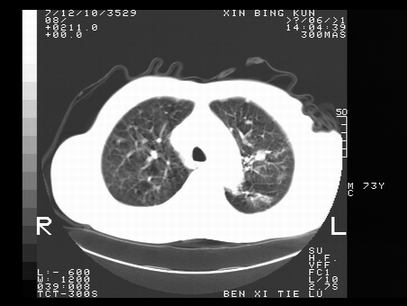

标题: CT10820:男,73岁,病史肺TB,现病史肺炎,直肠CA术后 [打印本页]

标题: CT10820:男,73岁,病史肺TB,现病史肺炎,直肠CA术后

双肺间质改变,依据病史双肺多发结节灶考虑转移,少量胸水.

1.两肺结核.2.两肺多发转移瘤.3右侧少量胸腔积液4.主动脉钙化.

双肺多发结节及条片状致密影,右侧少量胸腔积液。临床:直肠ca术后,肺tb病史。综合考虑:1 双肺转移!2 继发性肺结核合并感染!

此人病史较复杂,原有肺结核,直肠癌术后。肺部病灶形态亦呈多形性。因此,不可仅以一种病来解释肺部的病变。双肺多发的类圆形结节灶,结合病史还是首先考虑转移瘤,而双肺其余病灶还需结合化验室检查,结核或肺部感染在无其它检查资料的情况下不好排除。还是那句话----放射科医生不是开照像馆的,我们也是医生,看片一定要多结合临床及其它检查资料。要当一名合格的放射科医生,并不比当一名临床医生容易,我们可别把自已不当医生看。

两肺多发结节影,并见滋养动脉与其相连,考虑 两肺转移. 右侧胸腔积液考虑胸膜转移.

左肺上叶下叶背段,右肺中下叶见多发斑片状、条索状高密度影,兵变周围小结节影形成“树芽”样改变。 左肺上叶舌段近前胸壁处及右肺中叶内侧段见结节影。右侧胸膜腔内见液体密度区。纵隔内未见明确增大淋巴结。考虑左肺上叶舌段近前胸壁处及右肺中叶转移瘤可能性大。两肺继发型肺结核。右侧胸腔积液。